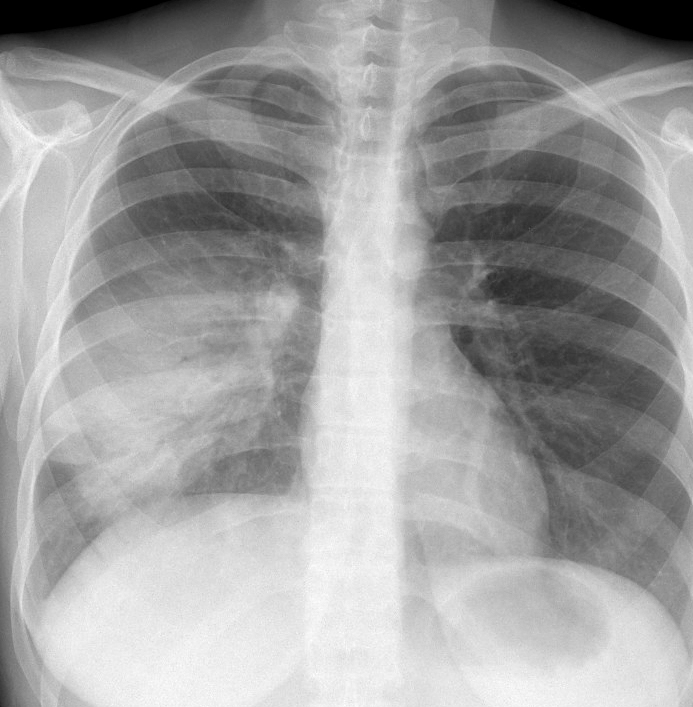

Gallery Pneumonia Case 11 RLL pneum PA

Case 11 RLL pneum PA